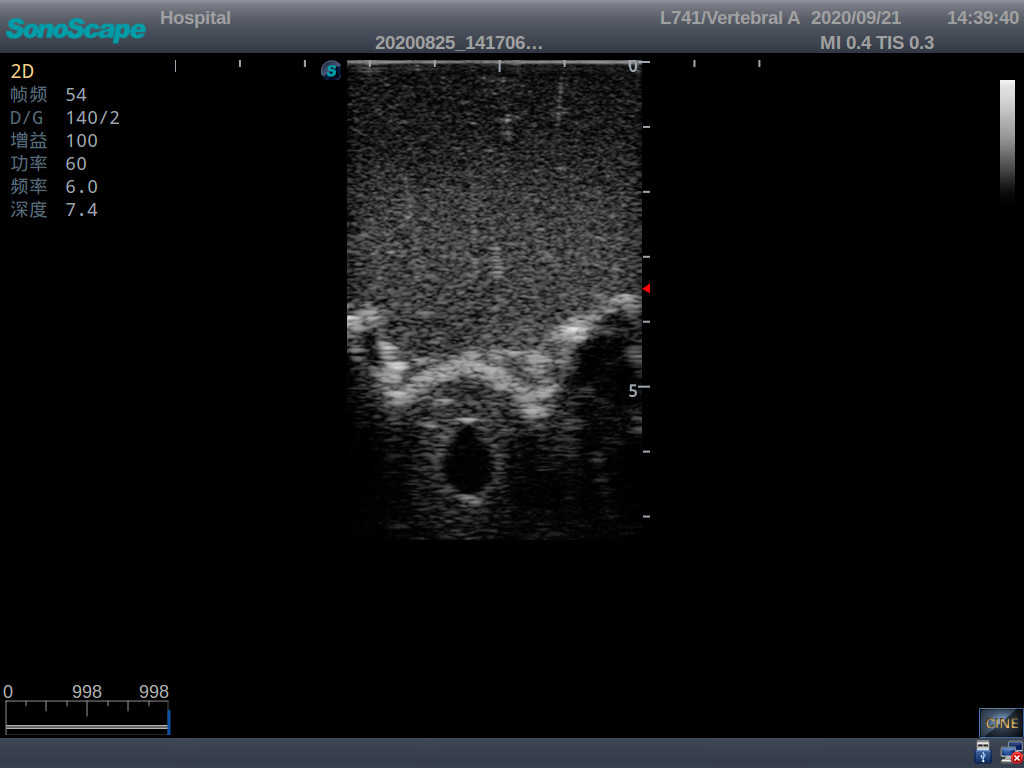

Adult Lumbar Puncture Ultrasound Training Model

This model is an ideal choice for ultrasound-guided adult lumbar puncture training with true-to-life skin feel and touch, accurate anatomical structures as well as real clinical ultrasound images. Realistic resistance to needle tips and correct landmarks provide excellent hands-on experience.

2)  Real clinical ultrasound images